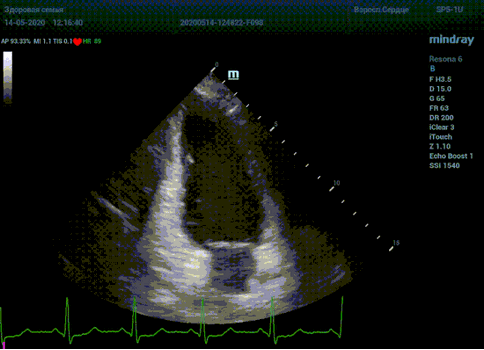

Что могут предложить современные приборы? Приборы нашего времени являются мощными вычислительными машинами, способными обрабатывать полученную информацию даже без помощи человека. Система автоматического вычисления фракции выброса – AUTO EF на приборах серии Resona компании Mindray сделает все за вас. За пару секунд прибор сам отыщет нужную фазу сердечного цикла и произведёт измерение и расчеты, а также покажет график изменения объема в сердечном цикле. От Вас требуется только получить качественное 4С и 2С сечение. Впрочем, прибор всегда оставляет возможность коррекции, если доктор имеет свое мнение на расположение точек планиметрии или момента измерения по ЭКГ каналу.